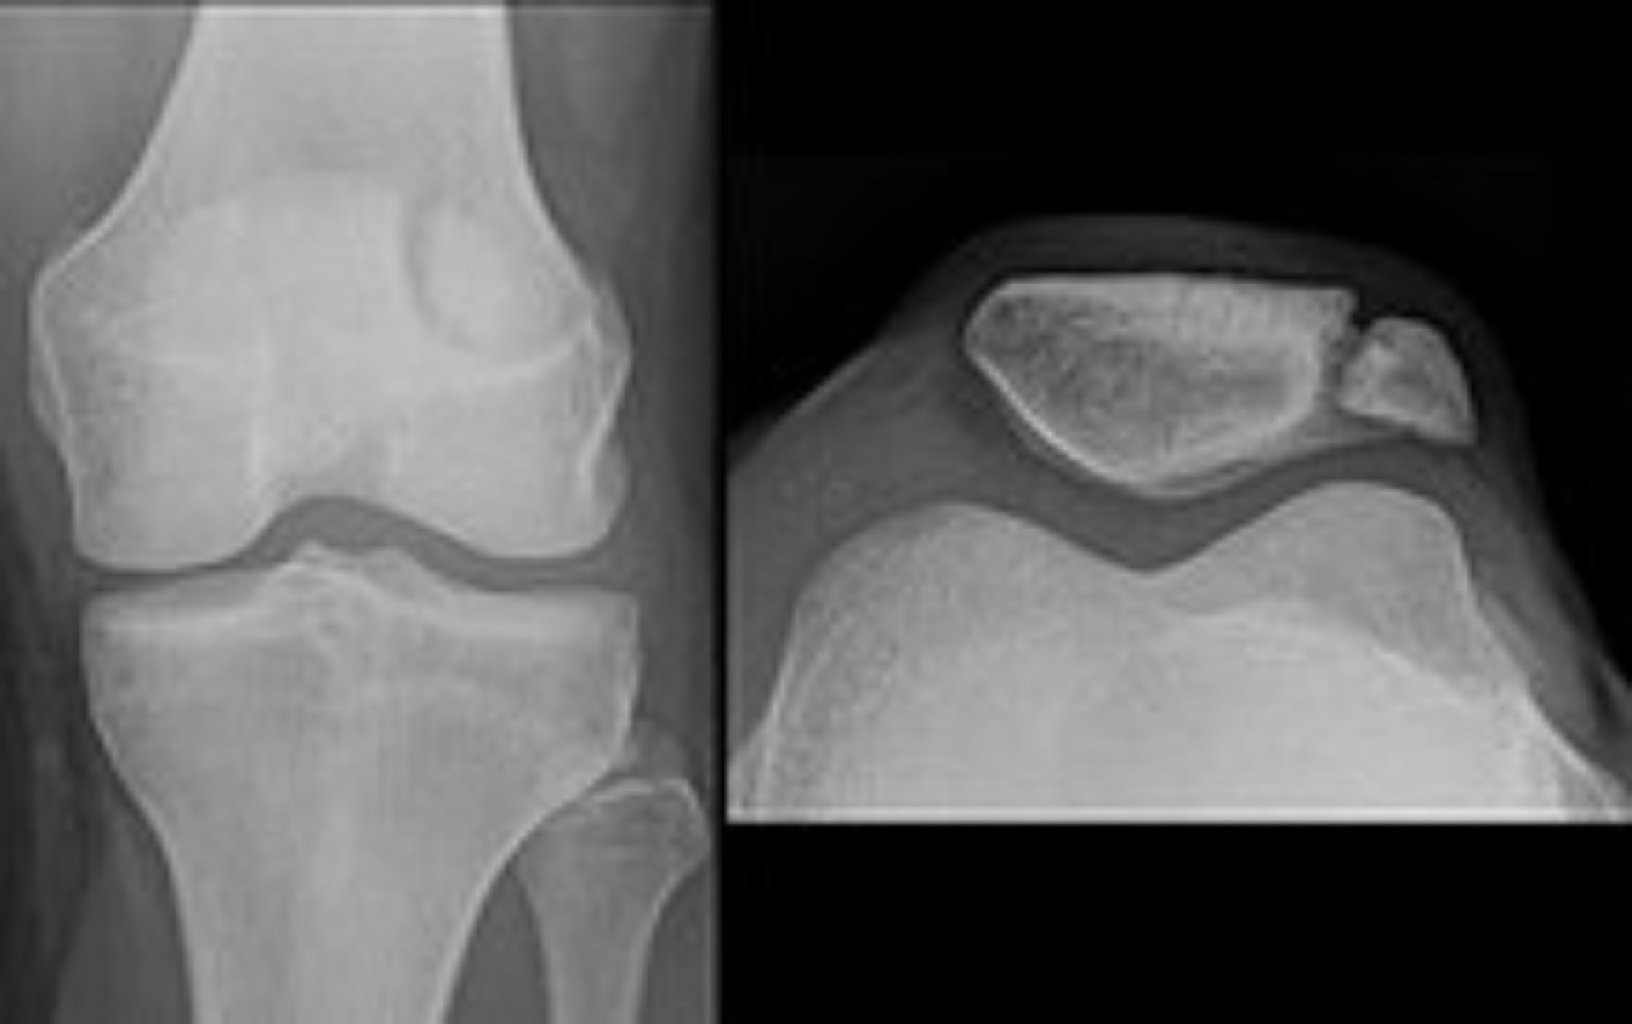

Diz Ağrılarının Səbəbləri Travma və Zədələnmələr: Sınıqlar: Diz sümüklərinin qırılması. Bur ...

Səbəbləri Diz qapağının sınıqlarının əsas səbəbləri arasında: Doğrudan zərbə: Diz qapağına doğ ...